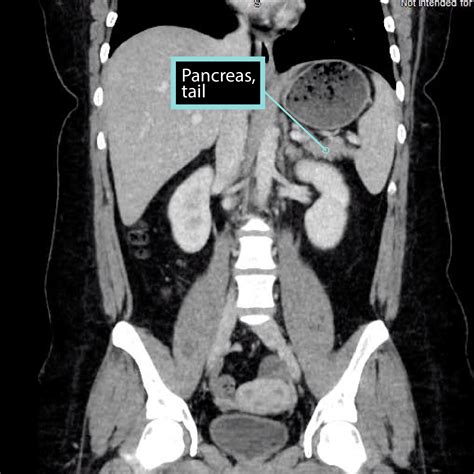

Pancreas Anatomy

Understanding the pancreas on CT scans is crucial for diagnosing and managing various pancreatic conditions. Computed Tomography (CT) scans provide detailed images of the pancreas, aiding in the detection of diseases such as pancreatitis, pancreatic cancer, and cysts. This blog post will delve into the importance of CT scans in pancreatic imaging, the preparation required for the procedure, and the interpretation of results.

CT scans are a cornerstone in the diagnostic process for pancreatic diseases. They offer high-resolution images that can reveal abnormalities in the pancreas, such as inflammation, tumors, or cysts. The detailed visualization provided by CT scans helps healthcare professionals make accurate diagnoses and develop effective treatment plans.